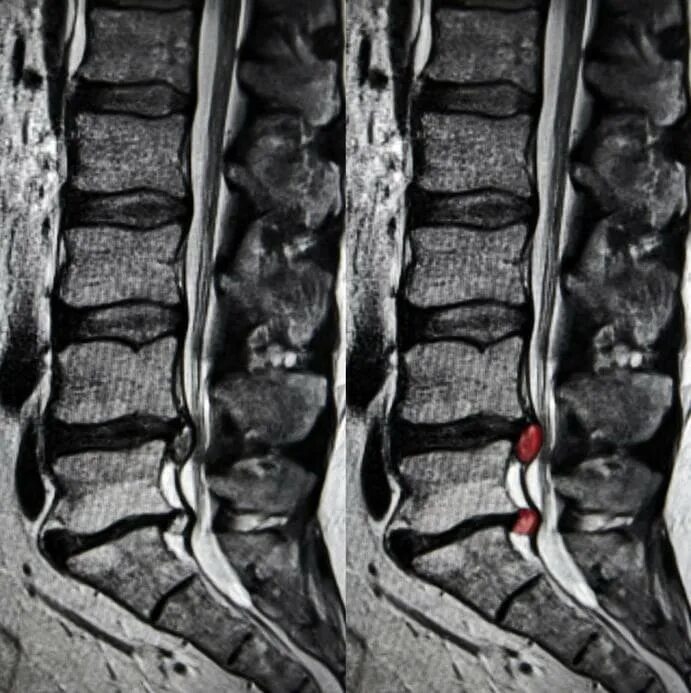

Остеохондроз l5 s1 дисков